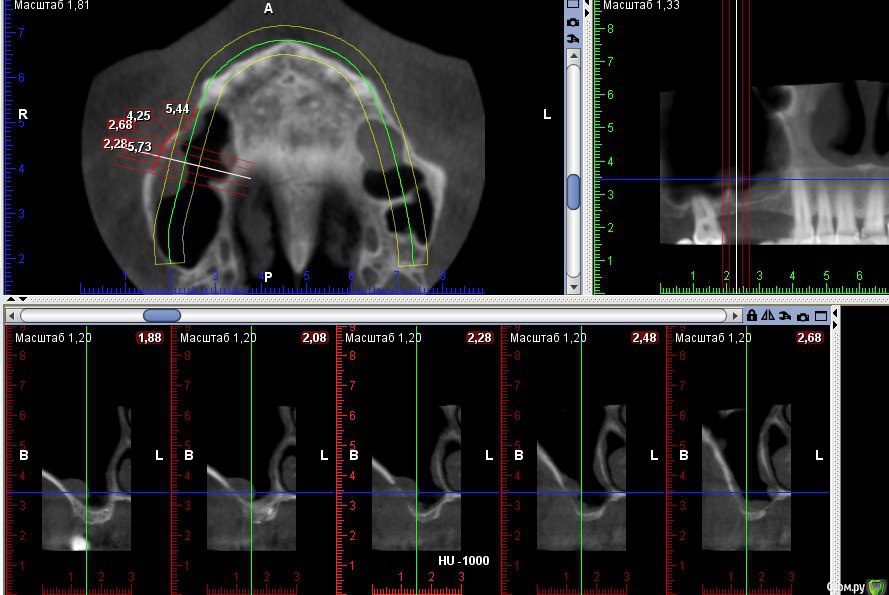

Kovalov Igor Опубликовано 19 мая, 2016 Поделиться Опубликовано 19 мая, 2016 (изменено) Здравствуйте уважаемые форумчане! Нужен совет по повторному синуслифтингу....3 месяца назад проводилась попытка синуслифтинга в 1 сегменте, отсутствие 14,15,16 зубов ... Разрез, формирование окна, в этом случае выбрал вход в синус с двух окон в проекции 14 и 16, получить перфу возле септы в области 16 когда отслаивал ... 14 отслойка без проблем... закрыл окна мембраной и ушил отправил погулять на 2,5-3 месяца.Вопрос как поступить ? Сделать одно большое окно? Как быть со спайками и как сложно их отделять ? Мембрану под перфу не подложил так как не делал ниразу этого... Кт после 3х месяцев ... Изменено 19 мая, 2016 пользователем Kovalov Igor Ссылка на комментарий

kriokov Опубликовано 19 мая, 2016 Поделиться Опубликовано 19 мая, 2016 пошел бы стандартно одним окном, да и первый раз думаю надо было одним окном идти, там не полная септа.Иногда приходиться остро работать на спайках как при расщеплении. Не знаю, но мне здесь одно здоровое окно видиться. И наверное зря Вы септу не спилили или не выкусили при первом заходе, если решили через три мес на повторный идти. Синус не плохо выглядит, думаю нормально все будет. 6 Ссылка на комментарий

red_butler Опубликовано 21 мая, 2016 Поделиться Опубликовано 21 мая, 2016 Куда вы 2гр L сыпите та? Тромбуете штоль?Даже еще раз пересмотрел срезы, Вы считаете что на такой операционной площади и при таком строении синуса расход будет меньше? 3 Ссылка на комментарий

Kovalov Igor Опубликовано 21 мая, 2016 Автор Поделиться Опубликовано 21 мая, 2016 Даже еще раз пересмотрел срезы, Вы считаете что на такой операционной площади и при таком строении синуса расход будет меньше?Ушло 2 грамма вы правы! ))) Спасибо всем за советы , ошибки были в первом случае малое и высоко расположенное окно, сделал в этот раз одно большое окно, спайки были только по периметру окна , было ощущение что окно начало заростать костью через три месяца, будто пластинка была поверх мембраны , может показалось ...Отслаивал до септы, графт 1,5 гр. в синус и 0,5 латерально от винтов и укрыл мембраной 25*25 владмива, мембрана не понравилась если честно ) Ссылка на комментарий